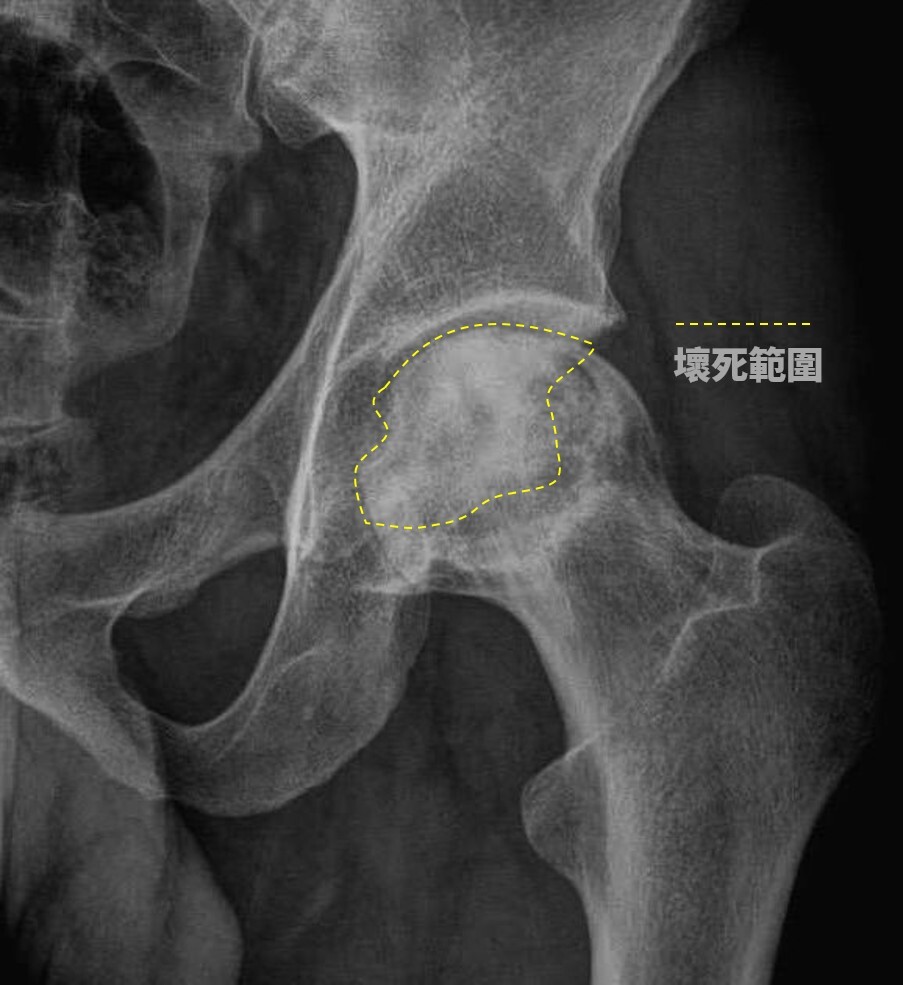

▲ 醫師提醒,酗酒對骨骼的影響主要體現在骨細胞血液中的栓塞,影響脂肪代謝,進而引發股骨頭缺血性壞死(圖/ 朴子醫院提供)

賴彥州醫師解釋,酗酒對骨骼的影響主要體現在骨細胞血液中的栓塞,影響脂肪代謝,進而引發股骨頭缺血性壞死。兩位患者的情況顯示,股骨頭已出現半月狀,即軟骨下方的骨頭已經壞死,且關節面已崩塌,為改善患者生活品質,建議進行半人工髖關節置換手術,手術後,兩位患者康復良好,不再感到疼痛,能夠自如地行動。然而,賴醫師提醒患者在康復期間需謹慎,避免過度彎腰、蹲下、提重物或跑跳,以確保手術效果最大化。